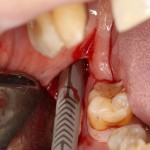

В отличие от костных блоков, делать забор аутокостной стружки можно в любом месте челюсти. Например, отдельным доступом через минимальный разрез:

или, непосредственно, со скелетированного участка операционной раны. Можно даже доступ для синуслифтинга сделать с помощью остеохарвестера, а заодно — собрать аутокостную стружку:

В общем, каждый выбирает методику забора аутокостной стружки, исходя из собственного опыта и пожеланий, а также клинической ситуации. Например, одному моему пациенту не понравились ощущения при использовании скребка Micross. Во время следующей операции мы проводили забор стружки с помощью вращающегося харвестера.